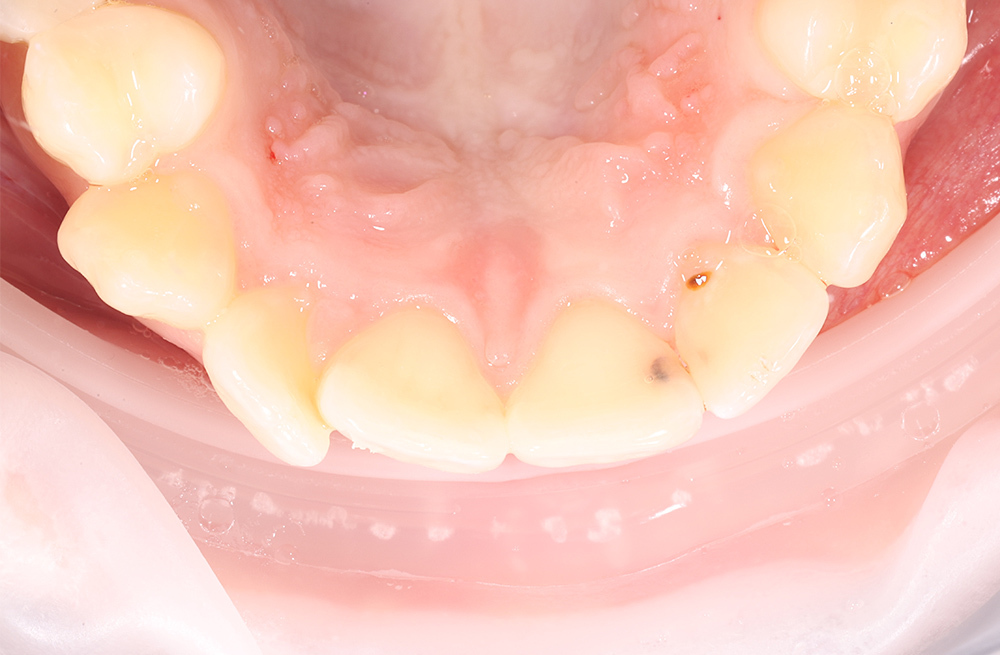

Лечение кариеса дентина у пациента, готовящегося к ортодонтии